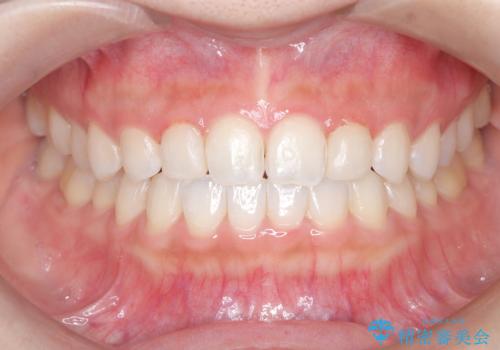

【ダイレクトボンディング】歯を削らずに綺麗にしたい。

- 矯正治療終了後、矮小歯の修復を希望された患者様です。

治療選択肢として、セラミッククラウン、ラミネートベニア、ダイレクトボンディングを提示したところなるべく歯を削りたくないとのことでダイレクトボンディングにて治療を行いました。

デメリットとして経年劣化が起こることによる変色リスク及びセラミックに比べ汚れがつきやすいことが挙げられます。